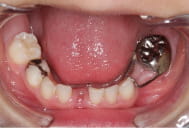

ディスタルシュー

6才臼歯が生える前に、手前の乳歯が抜けてしまった場合に装着します。

定期検診で経過をみて、6歳臼歯が生えてくる時期に装置をはずします。